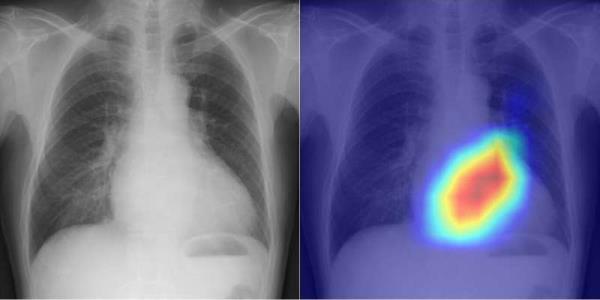

瓣膜性心脏病是心力衰竭的原因之一,通常使用超声心动图进行诊断。然而,这种技术需要专门的技能,因此相应的缺乏合格的技术人员。与此同时,胸部x线摄影是识别疾病(主要是肺部疾病)的最常见检查之一。尽管在胸片上也能看到心脏,但迄今为止,人们对胸片检测心脏功能或疾病的能力知之甚少。

许多医院都进行胸部x光摄影或胸部x光检查,进行这些检查所需的时间很少,这使得它们非常容易获得和可重复。因此,由大阪城市大学医学研究生院诊断和介入放射学专业的上田大久博士领导的研究小组认为,如果可以通过胸部x光片确定心脏功能和疾病,那么这项测试可以作为超声心动图的补充。

上田博士的团队成功开发了一种利用人工智能从胸部x光片中准确分类心脏功能和瓣膜性心脏病的模型。由于在单个数据集上训练的人工智能存在潜在的偏见,导致准确性低,因此该团队将目标对准了多机构数据。

因此,在2013年至2021年期间,从四个机构的16,946名患者中收集了22,551张胸片和22,551张超声心动图。以胸片为输入数据,超声心动图为输出数据,训练AI模型学习连接两个数据集的特征。

人工智能模型能够精确地对六种选定的瓣膜性心脏病进行分类,其曲线下面积(AUC)的范围从0.83到0.92。(AUC是表示AI模型能力的评级指标,使用的值范围为0到1,越接近1越好。)在检测左心室射血分数(监测心功能的重要指标)的40%截止时,AUC为0.92。